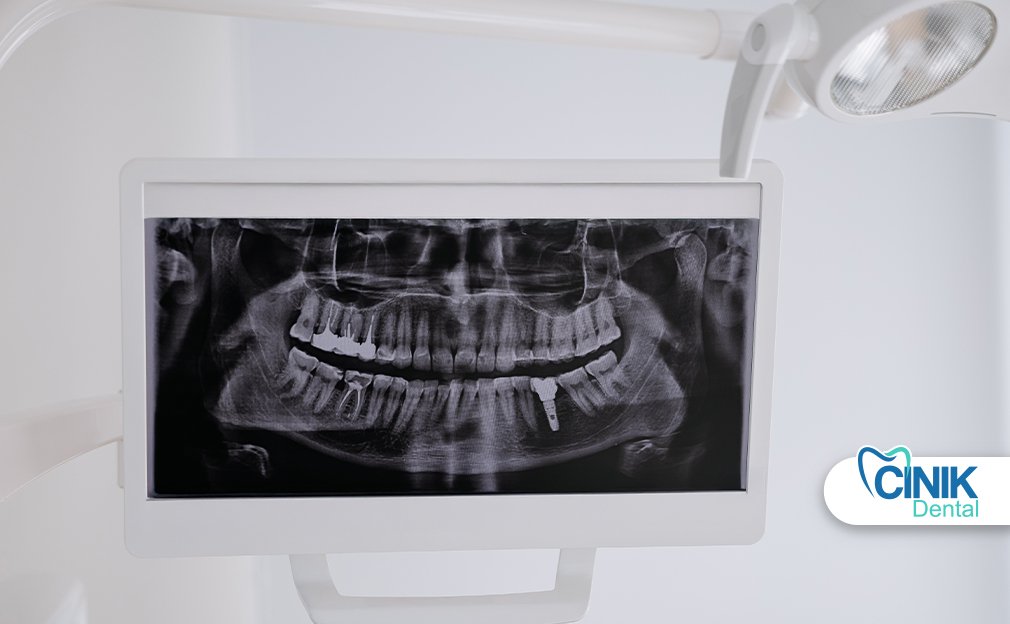

Panoramic dental X-rays provide a single, wide-view image of the entire mouth, including teeth, jaws, and surrounding bone structures. They are commonly used in orthodontics, oral surgery, and complex diagnostic cases to assess tooth position, jaw anatomy, wisdom teeth, and hidden pathologies such as cysts or tumors. The procedure is quick, painless, noninvasive, and uses a relatively low radiation dose compared to traditional X-rays.

A panoramic dental X-ray is a broad view capable of capturing the whole mouth in a single image. A patient’s head remains still while a rotating X-ray unit moves around them, allowing dentists to examine bone structure, teeth position, and abnormalities. Such radiographs are important in orthodontics, oral surgery, and when traumatic injuries may require extensive examination. Simultaneously, the lower dose of radiation and ease of obtaining images suit growing children with multiple teeth changing (Puricelli, 2009).

Panoramic dental X-rays display the entire jaw in a single image and are employed to determine the position of teeth, bone structure, and potential abnormalities. Dentists take panoramic X-rays for several reasons. First, they allow assessment of bone anatomy and pathology, dental development, and the extent of dental treatment. Second, they evaluate the mandible and maxillofacial region for certain lesions, cysts, and tumours not visible through intraoral films. Third, they detect gross caries, periodontal disease, or other pathology overlooked on intraoral films. Lastly, they are valuable for identifying unerupted teeth, especially wisdom teeth, and establishing their relationship to adjacent teeth (Ozmen and Basak Ayna, 2024).

Panoramic radiographs are a simple and widely used technique in dental specialties that involve synchronized rotation of an X-ray source and a stationary image receptor around the patient's head. This imaging method captures the entire maxillomandibular structure, including dental arches and related structures. It is beneficial because it involves a lower radiation dose, costs less, and images a larger area compared to intraoral radiographs. Panoramic radiography is recommended for patients with transitional or permanent dentition and can evaluate teeth, bone lesions, fractures, and foreign bodies (Couto Ramos et al., 2016).

A panoramic dental X-ray machine consists of a circular tube that emits the X-ray beam and a flat rectangular plate that receives the X-ray projection. The patient is positioned between the tube and the plate so that the X-ray beam is parallel to the plane of the teeth and the flat plate remains perpendicular to the horizontal plane passing through the center of the condyles. At the beginning of the exposure, the tube and the plate are positioned at an angle adjacent to the midline of the patient’s skull. The movement of the tube is diverging, while the plate moves in a horizontal straight line along the midline. At the completion of the action, the tube and the plate are positioned at the same angles but on opposite sides of the skull. Since the tube rotation occurs synchronously, while the tube and the plate are moving, a series of overlapping X-ray images are taken; the whole process lasts between 12 and 24 seconds.

The article explained panoramic dental X-rays, large images that capture the entire jaw’s teeth position, surrounding bone structure, sinuses, and possible tumors, cysts, or infections. A dentist may recommend one to collect comprehensive information about a patient’s dental health, especially when planning orthodontic, surgical, or wisdom tooth removal procedures. The X-ray uses a minimal dose of radiation and is noninvasive and painless.